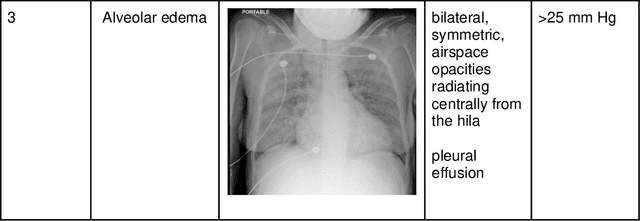

Abstract:Background: Clinical management decisions for acutely decompensated CHF patients are often based on grades of pulmonary edema severity, rather than its mere absence or presence. The grading of pulmonary edema on chest radiographs is based on well-known radiologic findings. Purpose: We develop a clinical machine learning task to grade pulmonary edema severity and release both the underlying data and code to serve as a benchmark for future algorithmic developments in machine vision. Materials and Methods: We collected 369,071 chest radiographs and their associated radiology reports from 64,581 patients from the MIMIC-CXR chest radiograph dataset. We extracted pulmonary edema severity labels from the associated radiology reports as 4 ordinal levels: no edema (0), vascular congestion (1), interstitial edema (2), and alveolar edema (3). We developed machine learning models using two standard approaches: 1) a semi-supervised model using a variational autoencoder and 2) a pre-trained supervised learning model using a dense neural network. Results: We measured the area under the receiver operating characteristic curve (AUROC) from the semi-supervised model and the pre-trained model. AUROC for differentiating alveolar edema from no edema was 0.99 and 0.87 (semi-supervised and pre-trained models). Performance of the algorithm was inversely related to the difficulty in categorizing milder states of pulmonary edema: 2 vs 0 (0.88, 0.81), 1 vs 0 (0.79, 0.66), 3 vs 1 (0.93, 0.82), 2 vs 1 (0.69, 0.73), 3 vs 2 (0.88, 0.63). Conclusion: Accurate grading of pulmonary edema on chest radiographs is a clinically important task. Application of state-of-the-art machine learning techniques can produce a novel quantitative imaging biomarker from one of the oldest and most widely available imaging modalities.